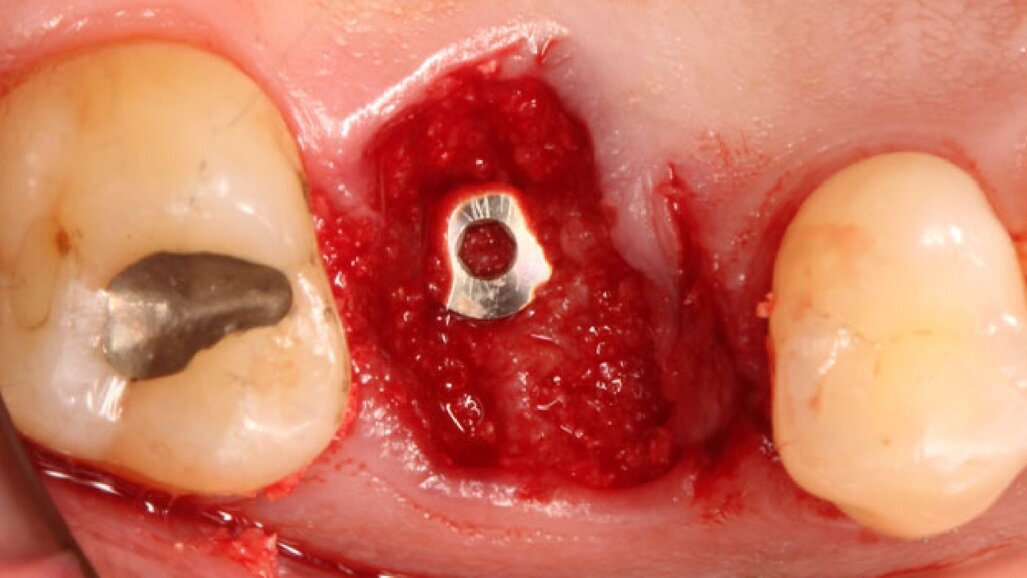

Dopo l’esecuzione dell’anestesia locale, il dente è stato rimosso e l’alveolo pulito dai residui del legamento parodontale. È stato inserito l’impianto (Zimmer TSV, Zimmer, Parsippany) 4.1 x 11,5 TSVM posizionato seguendo il protocollo consigliato dal produttore (Fig. 3). L’impianto è stato inserito a livello della cresta alveolare. È stato avvitato lo scan-abutment (Zfx Intrascan Matchholder, Zfx,). È stata rilevata un’impronta ottica intra-operatoria dell’emiarcata in cui è stato posizionato l’impianto con lo scan abutment (Fig. 3). Il gap tra l’osso vestibolare e l’impianto è stato riempito con Bio-Oss (Geistlich Pharma) (Fig. 4). Al termine della chirurgia è stato progettato e fresato il provvisorio, che è stato applicato appena pronto, dopo aver inserito la matrice in collagene volumetricamente stabile Fibro-Gide (Geistlich Pharma) precedentemente imbibita con il gel a base di polinucleotidi e acido ialuronico Regenfast (Officine Bio-Farmaceutiche Mastelli), al di sotto della vite stessa (Figg. 5, 6). Data l’accuratezza della vite non sono state necessarie suture. Al termine della procedura è stata eseguita una radiografia di controllo (Fig. 7).

Fig. 4_Inserimento implantare con zappatura del gap con Bio-Oss.